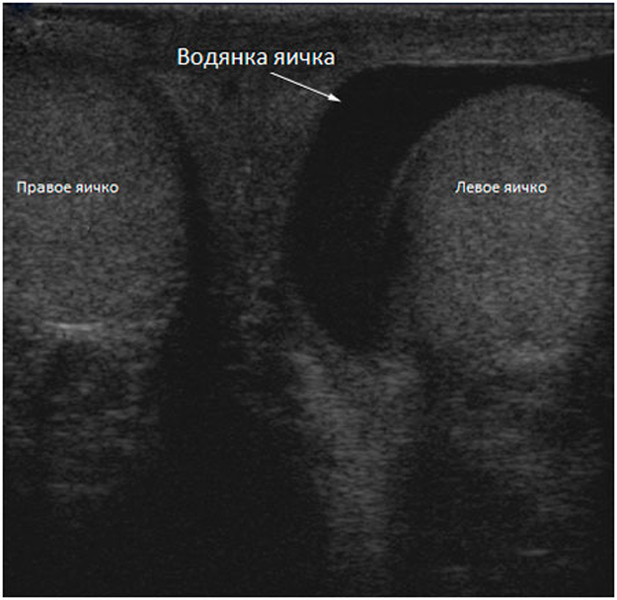

УЗИ мошонки (дети до 12 лет)

Для уролога ультразвуковое исследование мошонки - это самый точный и быстрый способ обнаружения большого количества патологий.

Данная процедура помогает дать оценку функциональным изменениям яичек, семенных канатников и других параметров. В нашей многопрофильной клинике «Парацельс» в Екатеринбурге ее можно пройти без какой-либо подготовки.